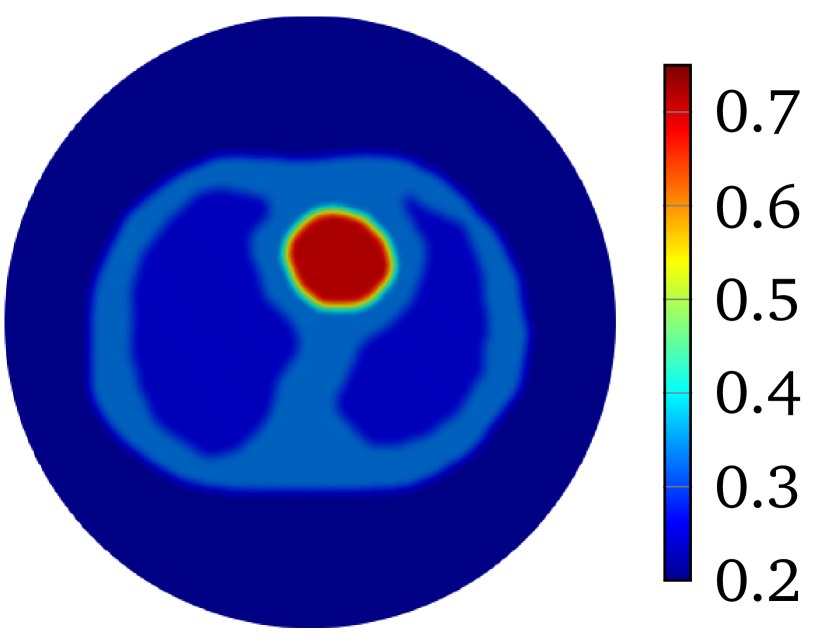

The LM-SCEM algorithm is used to reconstruct the distribution of . The initial guess is given as which is the value of the background tissue. The conductivity in the region for is supposed to be known. The values of are truncated to only update for with . The discontinuity caused by this truncation can be removed by applying (20) properly (either by mollification or simply by replacing the discontinuous values), but it does not cause any numerical problems since is small, so no special treatment was done in the following computation. The values of for the first 15 iterations are shown in Figure 4(a). The relative error is also given in Figure 4(b). With noise, the reconstruction with uniformly converges to with 15 iterations. The reconstructed is shown in Figure 5(a). To achieve a level of , it takes more than 40 iterations. A reconstruction with and is then carried out, but a similar speed of convergence and relative error is observed, result is in Figure 5(b). When the current pattern is further considered into the reconstruction, an obvious improvement of convergence is seen, and a relative error level is achieved with 14 iterations, the conductivity map is shown in Figure 5(c). Therefore, the convergence of LM-SCEM depends not only on the regularization parameter and the scaling parameter , but also on the current patterns for the measurements. Since indicates 0.1% of Gaussian noise in the simulated , the reconstructed result with is already good, and more iterations will not improve the result. To verify, a reconstruction with , and is carried out with (1% noise). Relative errors are shown in Figure 4(b), the reconstruction converges to within 7 iterations, and more iterations did not bring any improvements. The reconstructed result is given in Figure 5(d).